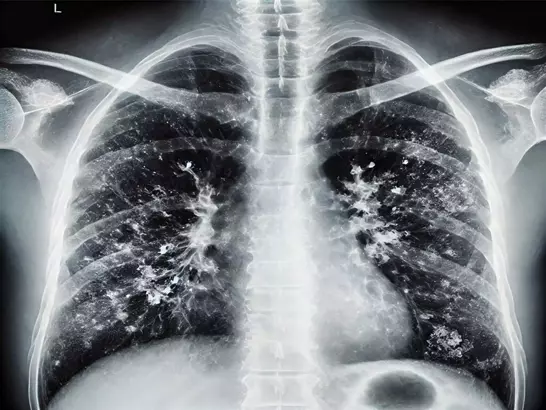

Grip olan 33 yaşındaki hastanın durumu kısa sürede bakteriyel zatürreye dönüştü. Zatürre ilerleyerek akut solunum yetmezliği sendromuna dönüştü; hastanın akciğerleri, kalbi ve böbrekleri iflas etmeye başladı.

BAZI AKCİĞERLER HİÇ İYİLEŞMEZÇıkarılan akciğerlerin analizi, tedavi anlayışı açısından da önemli bulgular ortaya koydu.

Doku incelemesi kapsamlı fibrozis ve bağışıklık sistemi hasarını gözler önüne serdi; söz konusu akciğerlerin hiçbir koşulda iyileşmeyip işlev kazanamayacağı anlaşıldı.

Şimdiye kadar ağır akut solunum yetmezliği sendromlu hastalar için 'tedavi uygulandıkça akciğerler iyileşir' deniyordu. Biz ilk kez biyolojik ve moleküler düzeyde kanıtladık ki bazı hastalar çift akciğer nakli olmadan hayatta kalamaz.